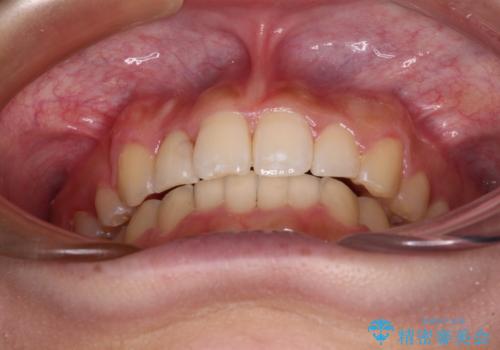

気になる八重歯を改善 補助装置併用のインビザライン治療

- 上顎の重なっている前歯を気にして来院された患者様です。

八重歯改善には抜歯が必要で、八重歯の移動量が多く、更には右側にずれている正中を改善する必要がありました。

インビザライン単体での治療は困難と判断し、補助装置により八重歯移動後にインビザラインを用いることとしました。

インビザラインでは治療期間が延びることが予想されたため、ワイヤー矯正を提案しましたが、セラミッククラウンが多く、壊すあるいは傷が付く可能性があることから、長期間であってもインビザラインを選択されました。